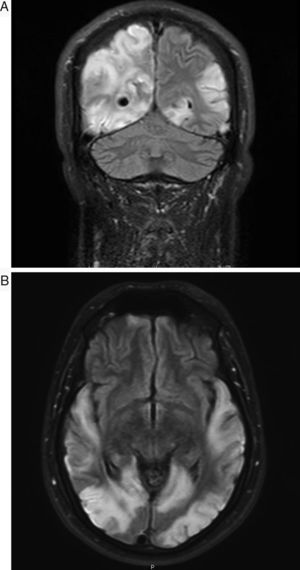

El síndrome de MELAS forma parte de las denominadas enfermedades mitocondriales, siendo un problema fundamental el no existir series largas de pacientes con el mismo defecto molecular y la misma manifestación clínica que permitan realizar estudios concluyentes sobre la efectividad de los diversos fármacos aplicados1. Presentamos el caso de un varón de 30 años, sin antecedentes de interés, que en enero de 2013 presentó episodio compatible con crisis epiléptica focal secundariamente generalizada, con posterior status epiléptico que precisó ingreso en la UVI. Se realizó, entonces, resonancia magnética (RM) craneal dónde se apreció únicamente engrosamiento cortical focal de giro lingual izquierdo sugiriendo como primera posibilidad diagnóstica displasia cortical focal. El paciente estuvo asintomático hasta principios de septiembre de 2014, cuando fue ingresado en nuestro centro tras haber presentado un cuadro brusco de pérdida de visión en hemicampo izquierdo. En una primera valoración neurológica presentaba en la exploración únicamente hemianopsia homónima izquierda y discreta dismetría en maniobra dedo-nariz en miembro superior izquierdo. El paciente sufrió un llamativo y rápido empeoramiento durante los días siguientes, desarrollando ceguera cortical, sordera cortical y afasia completa. Presentaba importante inquietud psicomotriz, en ocasiones agitación franca, con jergafasia continua y actos inmotivados. Su única forma de contacto con el exterior era mediante el tacto y reconocía a su mujer por el anillo que ella llevaba. Analíticamente destacaba una elevación de lactato tanto en sangre (2,7mM/l) como en líquido cefalorraquídeo (3,36mM/l), así como elevación de L-carnitina y carnitina total en sangre. La creatincinasa fue normal. No presentaba datos de miopatía en el electromiograma y la audiometría mostró la presencia de una hipoacusia neurosensorial bilateral leve. En una nueva RM se objetivó extensión importante de las lesiones con afectación cortical hemisférica izquierda (predominio occipital, parietal y temporal), hiperintensidades en secuencias T2 y FLAIR, con edema y zonas de efecto masa, así como restricción en la difusión. Presentaba también afectación hemisférica derecha occipito-parietotemporal de similares características, y alguna zona de necrosis cortical laminar (figs. 1 y 2A y B). La biopsia muscular mostró cambios inespecíficos y ausencia de cambios morfológicos diagnósticos de miopatía mitocondrial (no fibras rojo rasgadas, no fibras COX-negativas). El estudio genético fue positivo para la mutación A3243G. Durante su ingreso recibió tratamiento con fenitoína 100mg en pauta 100-50-100, levetiracetam 1.000mg/12h, clonazepam 0,5mg/12h, ubiquinol 200mg/8h, idebenona 90mg/8h, arginina 6g/8h, complejos vitamínicos (B2 riboflavina 50mg/8h, B1 Tiamina® 300mg/medio comprimido/12h, vitamina E 200mg/un comprimido al día/lunes, miércoles y viernes; vitamina C 2g al día). Se objetivó cierta mejoría evolutiva. Este caso presenta varios aspectos de especial interés. En primer lugar, la edad de presentación tardía, lo cual sucede en alrededor de un 20% de los casos. Destaca también el hecho de que el paciente no presentara afectación muscular. La afectación muscular es especialmente frecuente en pacientes portadores de la mutación A3243G. Distintos estudios han revelado que la mutación A3243G produce un defecto severo combinado de la cadena respiratoria en los mioblastos. En la biopsia muscular suelen encontrarse depósitos grasos y es habitual la presencia de fibras rojo rasgadas. El porcentaje de pacientes diagnosticados de MELAS (independientemente de la mutación) con biopsia negativa ronda el 10% según algunos trabajos2. También resulta de interés la evolución tan agresiva que presentó el cuadro, pasando en apenas 3 días de presentar únicamente una hemianopsia a un estado de ceguera, sordera y afasia mixta que imposibilitó de manera prácticamente total la comunicación del paciente con el medio. La sordera de origen central ha sido descrita muy raramente3. En lo referente al tratamiento recibido, los complejos vitamínicos (B2, B1, E y C) en este caso actuarían como sustancias antioxidantes, lo que parece útil para corregir el daño oxidativo, aunque tampoco existen estudios concluyentes sobre su efectividad4. Como dato a destacar además se inició tratamiento con L-arginina, precursor del óxido nítrico cuyos niveles han sido analizados en distintos trabajos, encontrándose una disminución de los mismos tanto en periodo agudo como en fase interictal en comparación con sujetos control. La arginina se considera uno de los fármacos más prometedores5,6 y, aunque sus mecanismos de actuación no son completamente conocidos, parece que tiene efecto en la regulación vascular, produciendo vasodilatación mediante aumento del óxido nítrico. Esto produciría un aumento de la capacidad aeróbica y una mejoría en el metabolismo muscular6. La administración se puede realizar vía infusión intravenosa en fase aguda, con una actuación rápida en menos de 24h, con mejoría sintomática. Sin embargo, los síntomas pueden empeorar en los días sucesivos si no se continúa una suplementación vía oral, con una dosis recomendada de unos 0,5g/kg/día. En la actualidad nuestro paciente recibe una dosis vía oral de arginina de 6g/8h. El paciente permaneció ingresado durante aproximadamente mes y medio, objetivando cierta mejoría evolutiva. Al alta obedecía una orden sencilla y era capaz de elaborar frases cortas y coherentes. Presentó discreta mejoría de la visión, actualmente distingue colores, formas y movimiento. Persiste déficit de lenguaje con parafasias, por lo que continúa realizando logopedia ambulatoria. En ningún momento se ha objetivado déficit motor. Mantiene tratamiento con complejos vitamínicos, arginina vía oral 6g/8h, clonazepam 0,5mg/8h, levetiracetam 500mg/12h y lacosamida 100mg/8h, habiéndose suspendido la fenitoína. Se mantiene estable y no ha vuelto a precisar nuevos ingresos hasta el momento.